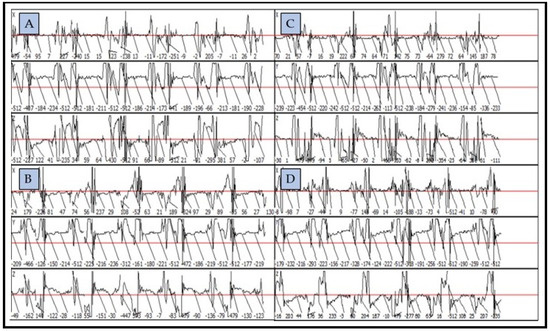

3.1. Descriptive Statistics for the Mean Impulse Numbers Recorded in the Lame and Sound Contralateral Legs of the Assessed Horses